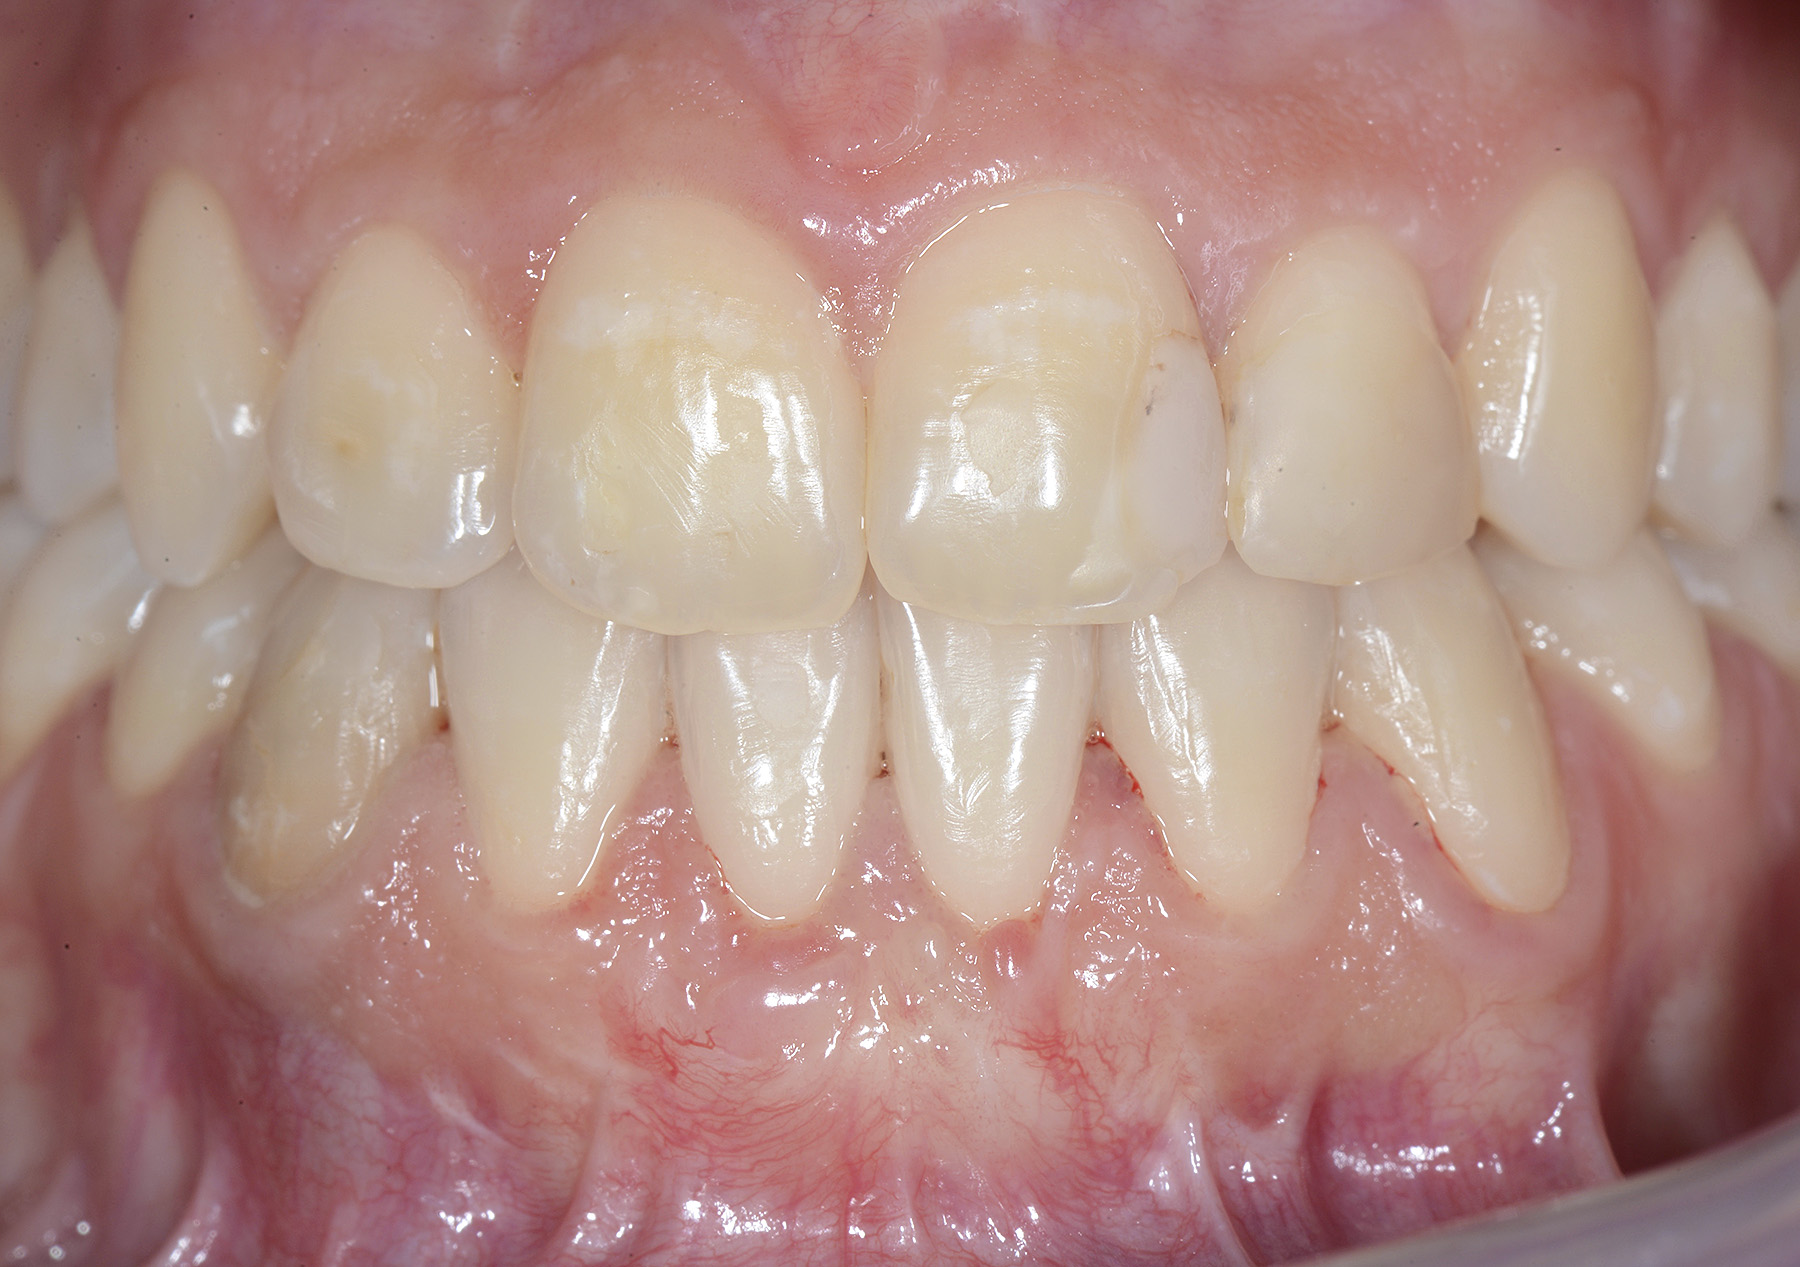

PREMESSA: in seguito all’estrazione dell’incisivo laterale superiore di destra, resasi necessaria per cause batteriche, si decide di affrontare il caso con il posizionamento di un impianto in sostituzione dell’elemento mancante dopo guarigione del sito infetto. Con tecniche rigenerative sia dei tessuti ossei mancanti a causa dell’infezione pregressa, sia dei tessuti gengivali che appaiono inizialmente troppo spostati in alto, si ripristina una corretta morfologia delle parabole (contorni) gengivali e delle papille interdentali (triangoli di gengiva tra due denti vicini).

Vengono utilizzati 2 tipi di provvisori: il primo, cementato ai denti vicini, viene utilizzato dal momento dell’estrazione del dente fino ad impianto osteointegrato (circa 6 mesi); il secondo, avvitato direttamente all’impianto, ha una funzione di prova estetica ma soprattutto di guida per la maturazione dei tessuti gengivali peri-implantari portandoli verso la maturazione completa prima di posizionare la corona finale in disilicato di litio.